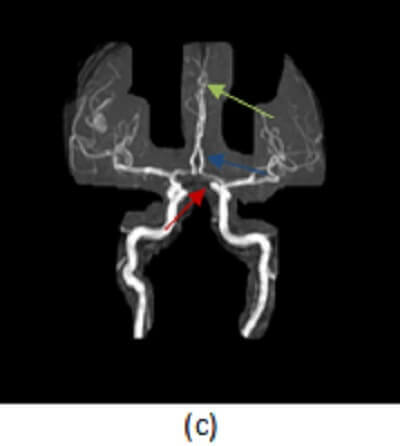

Diagnosis: Anterior cerebral artery territory infarct

Figure 1: (a) Noncontrast head CT demonstrates hypodensity and mass-effect involving the medial left frontoparietal lobes; (b) Increased restricted diffusion in this territory on DWI consistent with an acute infarct; and (c) MIP reconstructions from an MR angiogram demonstrate major segments of the anterior cerebral artery A1 (red arrow), A2 (blue arrow), A3 (green arrow).